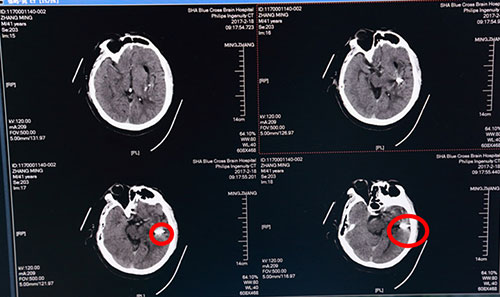

術(shù)后第二日頭顱CT:血腫基本清除,紅圈內(nèi)白色光點為穿刺針

術(shù)后第二日,復(fù)查頭顱CT示:左側(cè)基底節(jié)區(qū)血腫已基本清除干凈,術(shù)后一周再次復(fù)查頭顱CT示:左側(cè)基底節(jié)區(qū)血腫術(shù)后改變,血腫已基本清除,蛛網(wǎng)膜下腔滲出較前減少,金屬引流管撤除;術(shù)后一月復(fù)查全腦血管造影(DSA),出血點血管未見異常,排除腦動脈瘤破裂出血可能。目前患者精神奕奕,正在積極接受康復(fù)綜合治療,不日即可出院,回歸正常生活。